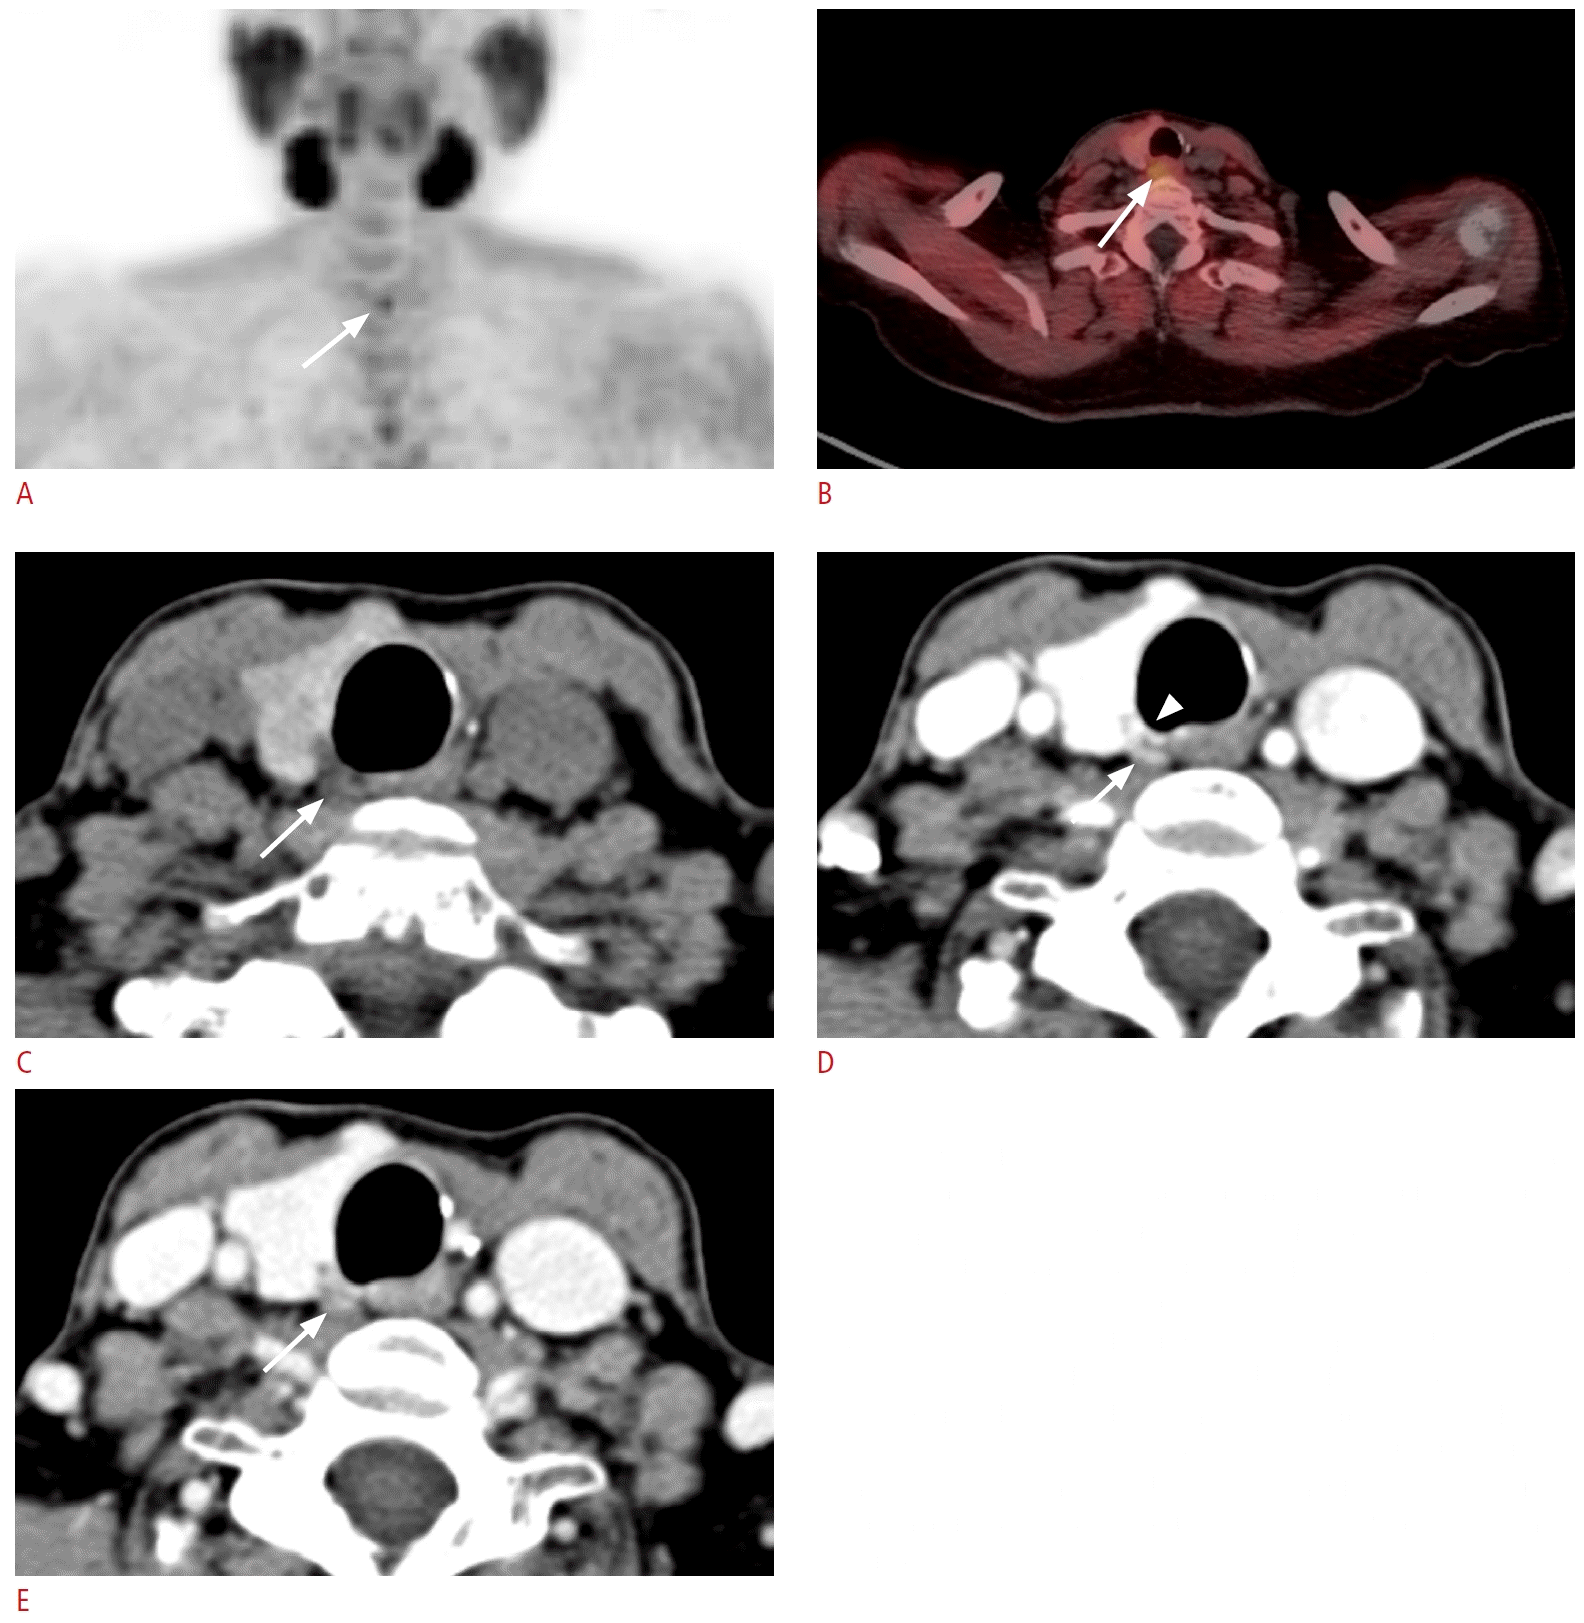

59. Patel CN, Salahudeen HM, Lansdown M, Scarsbrook AF. Clinical utility of ultrasound and

99mTc sestamibi SPECT/CT for preoperative localization of parathyroid adenoma in patients with primary hyperparathyroidism. Clin Radiol. 2010; 65:278–287.

63. Hoang JK, Sung WK, Bahl M, Phillips CD. How to perform parathyroid 4D CT: tips and traps for technique and interpretation. Radiology. 2014; 270:15–24.

66. Bahl M, Sepahdari AR, Sosa JA, Hoang JK. Parathyroid adenomas and hyperplasia on four-dimensional CT scans: three patterns of enhancement relative to the thyroid gland justify a three-phase protocol. Radiology. 2015; 277:454–462.

67. Vance-Daniel J, Curwen O, Stroud L, Gnanananthan V, Burney K, Jamal K. An assessment of enhancement patterns in abnormal parathyroid glands on three-phase CT imaging. Cureus. 2023; 15:e40166.